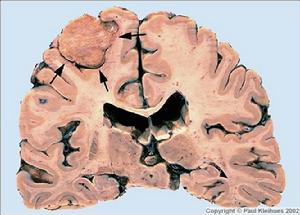

圖11.頭顱平片 顱底像對診斷本病有一定價值。可見中顱窩底骨質被破壞表現為密度減低,圓孔和棘孔擴大模糊不清岩骨尖骨質被破壞。腫瘤鈣化呈散在斑片狀或密度較均勻的條塊。